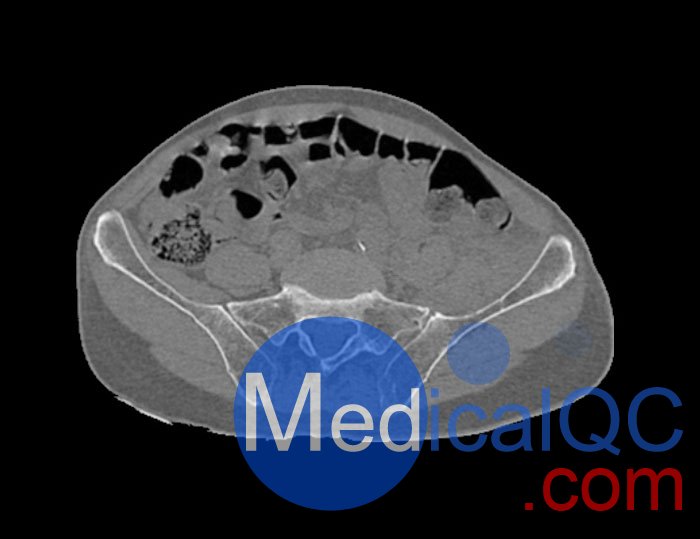

WEK54-01股骨頸骨折骨盆模型,WEK54-01骨盆模體詳細介紹:

WEK54-01股骨頸骨折骨盆模型,WEK54-01骨盆模體模擬沒有靜脈造影劑的骨盆(天然)。它覆蓋了整個骨盆,直到第五腰椎。

左側股骨頸移位骨折。

該模型可用于 CT(包括 CBCT)和射線照相,以評估和優(yōu)化成像性能和后處理應用,包括支持 AI 的應用。它也適用于培訓目的。

WEK54-01股骨頸骨折骨盆模型,WEK54-01骨盆模體提供了對軟組織和骨組織的詳細而逼真的模擬。空隙中填充著約-160HU的纖維素-聚合物復合材料。

WEK54-01股骨頸骨折骨盆模型,WEK54-01骨盆模體成像效果圖: